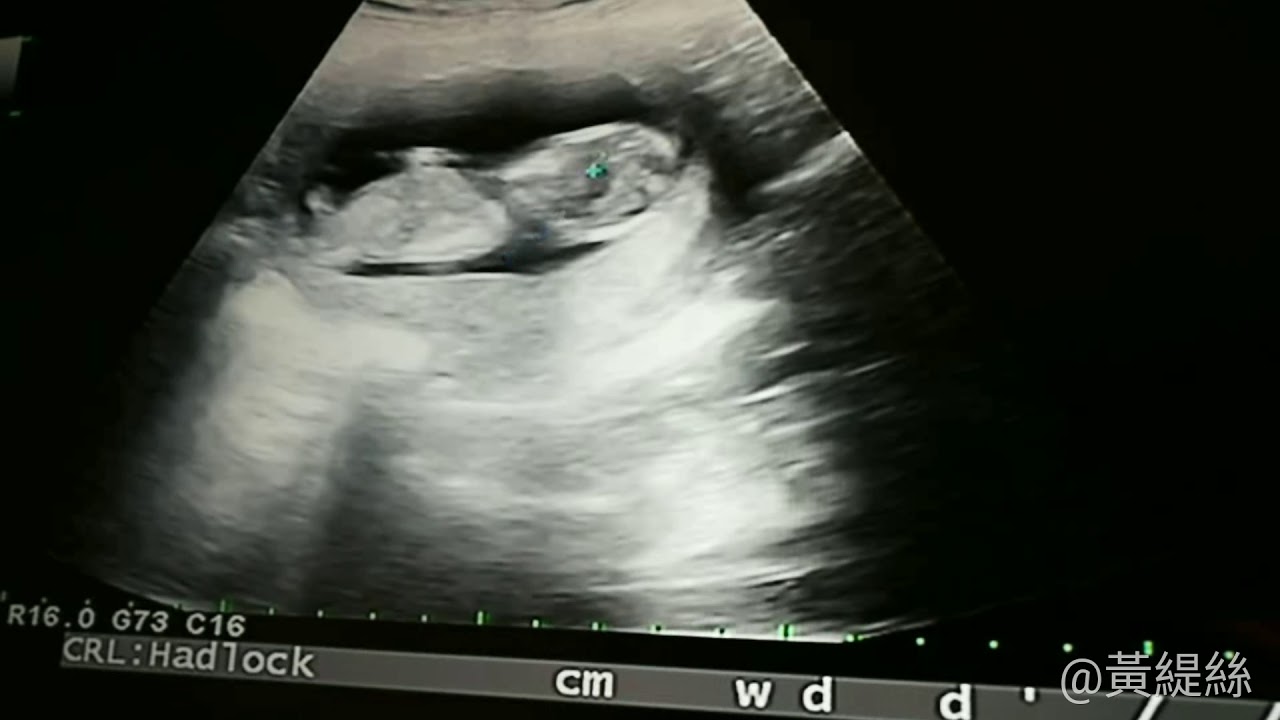

- 超音波檢查:確認胎兒心跳及發育狀況。